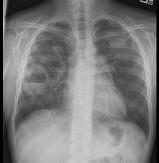

问题 男,35岁,发热,贫血,血尿,既往有副鼻窦炎,结合X线图像,最可能的诊断是 ( )

选项 A.肺脓肿 B.周围型肺癌 C.肺转移瘤 D.肺结核 E.韦格肉芽肿

答案 E